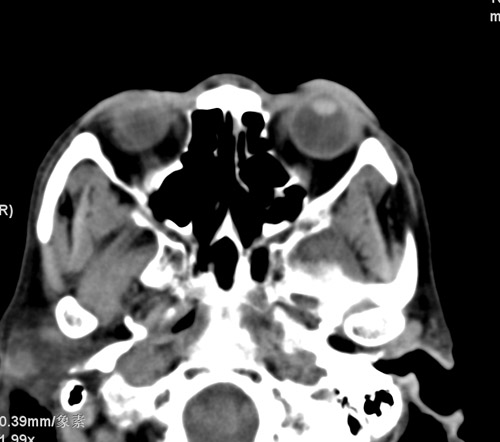

标题: CT17755:女,74 左鼻旁肿胀半年,临床以左上颌窦旁占位行CT [打印本页]

标题: CT17755:女,74 左鼻旁肿胀半年,临床以左上颌窦旁占位行CT

ct考虑鼻前庭囊肿 或鼻翼基底部慢性炎症,左上颌窦少许炎症 请指教

1)考虑左侧鼻前庭囊肿并感染。2)双侧上颌窦炎。

左侧鼻前庭囊肿并感染。双侧上颌窦炎。支持